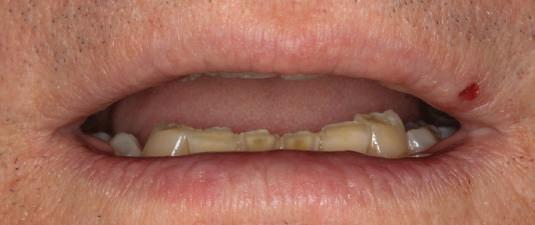

Pacientul prezenta dentiţie maxilară şi mandibulară eşuată datorită cariei secundare provocată de xerostomia post-iradiere. Pacientul suferise o disecţie cervicală radicală pentru înlăturarea carcinomului cu celule scuamoase la nivelul gâtului cu 9 ani înainte, urmată de radioterapie dar fără limită de ecranare. S-a utilizat o abordare stadializată pentru a evita protezele mobilizabile pe ţesuturile moi, extrem de uscate. Pacientul a optat pentru tratarea prioritară la nivel mandibular.

Fig. 9 prezintă bonturile de vindecare adiacente dinţilor naturali menţinuţi temporar, iar fig. 10 bonturile individualizate din prima etapă, inserate cu un contur gingival relativ bun şi fără recesie. Recesia era clar vizibilă în jurul tuturor bonturilor din prima etapă, după extracţiile adiacente şi plasarea implanturilor din a doua etapă (fig. 11). Atitudine: S-a decis îndepărtarea acestor bonturi şi amprenta corpului implantar al tuturor implanturilor astfel încât bonturile noi şi cele din prima etapă să fie frezate împreună pentru paralelism şi poziţionarea adecvată a marginii gingivale. Întrucât aceasta necesita îndepărtarea bonturilor din prima etapă care menţineau proteza provizorie, înainte de îndepărtarea tuturor bonturilor individualizate s-au plasat bonturi provizorii, cu scopul de a asigura poziţionarea adecvată şi dimensiunea verticală a restaurării provizorii. Aceste bonturi provizorii au menţinut apoi restaurarea temporară,

Cazul (3): Refrezarea bonturilor individualizate

Figurile

9. Bonturile de vindecare.

10. Bonturile individualizate în prima etapă.

11. Recesia evidentă în jurul bonturilor din prima etapă, după extracţiile adiacente şi inserarea implanturilor din faza a doua.

12. Bonturile refrezate şi noile bonturi individualizate.

în timp ce toate bonturile individualizate au fost fabricate şi/sau frezate în laborator. Fig. 12 prezintă plasarea bonturilor refrezate (la implanturile din prima etapă) şi bonturile individualizate noi (la cele din a doua etapă).